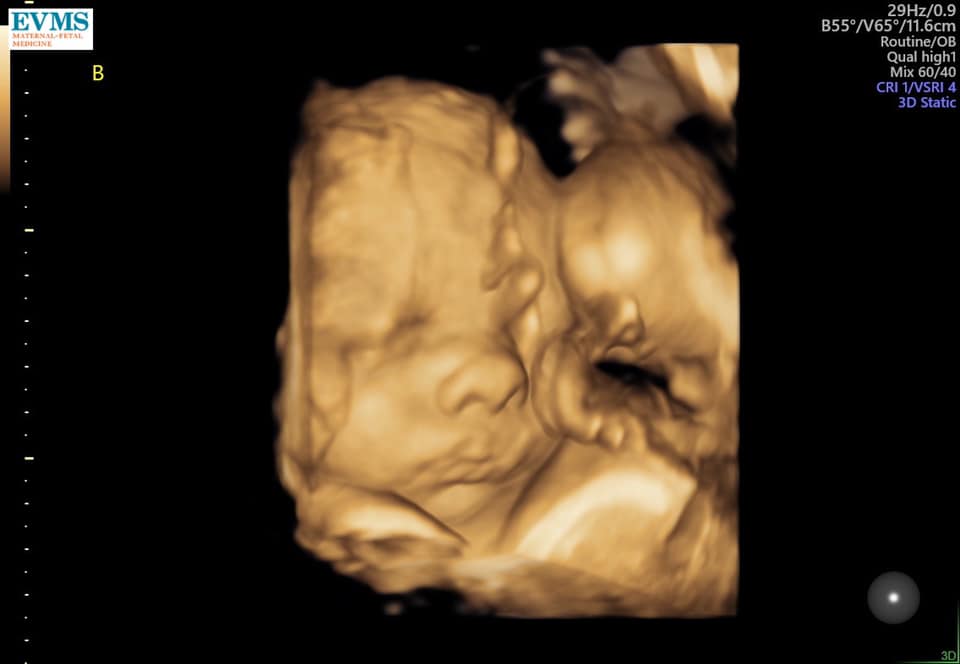

- Ultrasound Photos at 32 Weeks Pregnant With Twins

Ultrasound Photos at 32 Weeks Pregnant With Twins